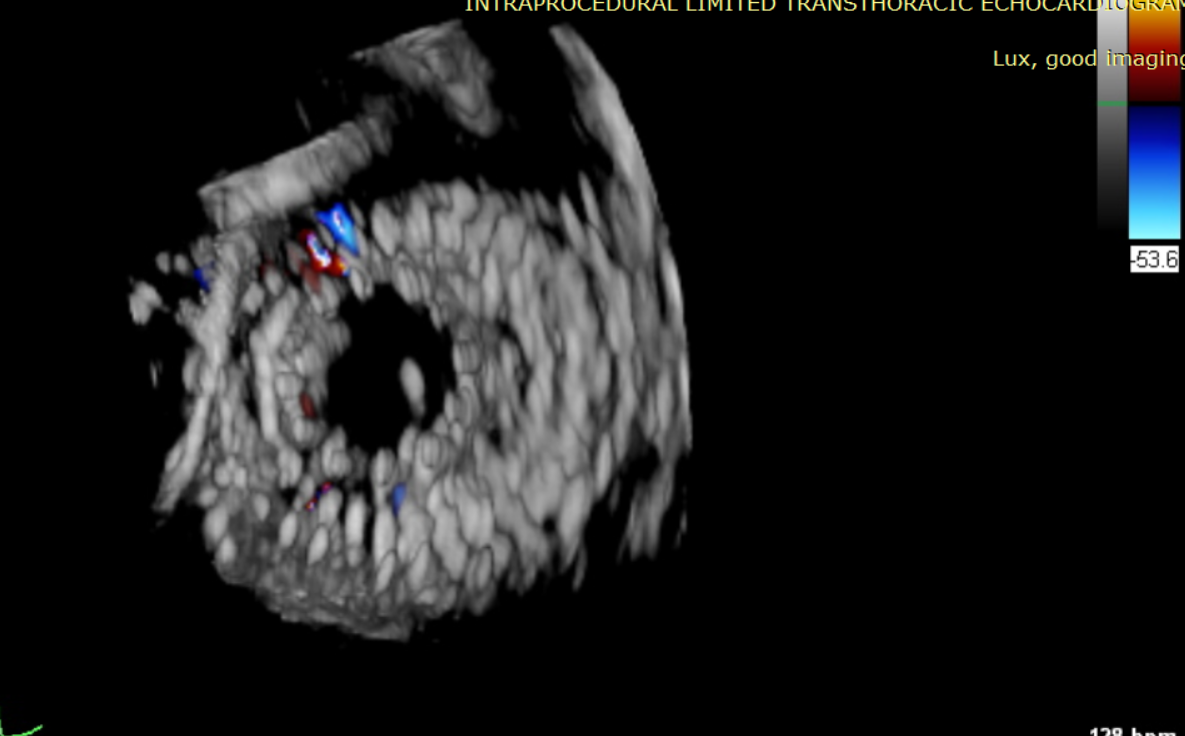

術前超聲提示大量三尖瓣反流

術中輸送器在超聲引導下調整位置

術后超聲提示無瓣周漏

術后超聲提示僅殘余輕微瓣周漏